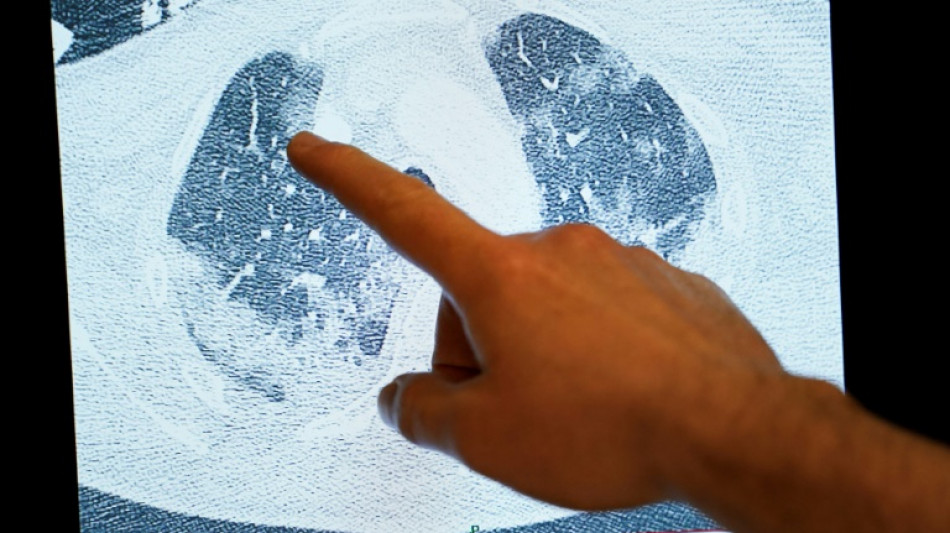

O estudo é baseado em ressonâncias magnéticas realizadas em 259 pacientes que foram hospitalizados pelo novo coronavírus entre 2020 e 2021. Os resultados foram comparados com exames realizados em cerca de 50 pessoas que nunca foram infectadas.

Cerca de um terço dos pacientes de covid apresentavam "anomalias" em vários órgãos - cérebro, pulmões, rins e, em menor medida, coração e fígado - meses depois de terem alta.

Os pesquisadores observaram, por exemplo, lesões na substância branca do cérebro, fenômeno que a literatura científica associa a uma leve perda cognitiva.

Os autores do estudo e observadores independentes acreditam que estes resultados fornecem uma possível explicação para a covid longa, ou seja, a persistência de sequelas duradouras meses após a infecção.

O estudo publicado na sexta-feira sugere que a covid longa "não se explica por insuficiências graves concentradas em um único órgão", mas que obedece a "uma interação entre pelo menos duas anomalias" em órgãos diferentes, afirma o pneumologista Matthew Baldwin, que não participou do estudo, no mesmo número da Lancet Respiratory Medicine.